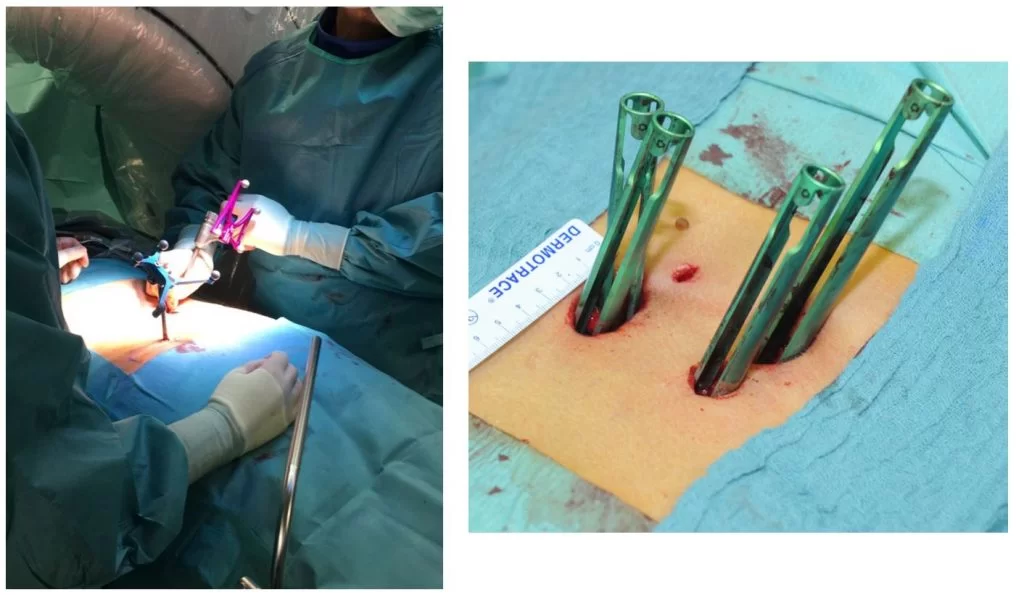

Η προσπέλαση μπορεί να είναι πρόσθια (δηλαδή από μπροστά, όπως πχ. συχνά στον αυχένα, Εικόνα 2), οπίσθια (όπως πχ. συχνά στη μέση, Εικόνα 3) ή και πλάγια (όπως πχ. σε τεχνικές όπως το XLIF κλπ.)

Επίσης, να σημειωθεί ότι υπάρχουν ελάχιστα επεμβατικές τεχνικές (διαδερμικές) οι οποίες επιτρέπουν πλέον αυτές οι επεμβάσεις να πραγματοποιούνται μέσα από μικρές τομές και με ελάχιστο τραύμα στους υγιείς ιστούς.

Οι σύγχρονες τεχνικές και η τεχνολογία επιτρέπουν πλέον η σπονδυλοδεσία να πραγματοποιείται με πολύ μικρές τομές και ελάχιστο τραύμα (και κατ’ επέκταση πόνο) για τον ασθενή. Η πιο σύγχρονη μέθοδος είναι η διαδερμική σπονδυλοδεσία με νευροπλοηγό (Εικόνες 4 – 6). Στην τεχνική αυτή, οι βίδες και οι ράβδοι τοποθετούνται μέσα από πολύ μικρές τομές και με τη βοήθεια της 3D-νευροπλοήγησης τα μοσχεύματα μπορούν να τοποθετηθούν με εξαιρετική ακρίβεια.